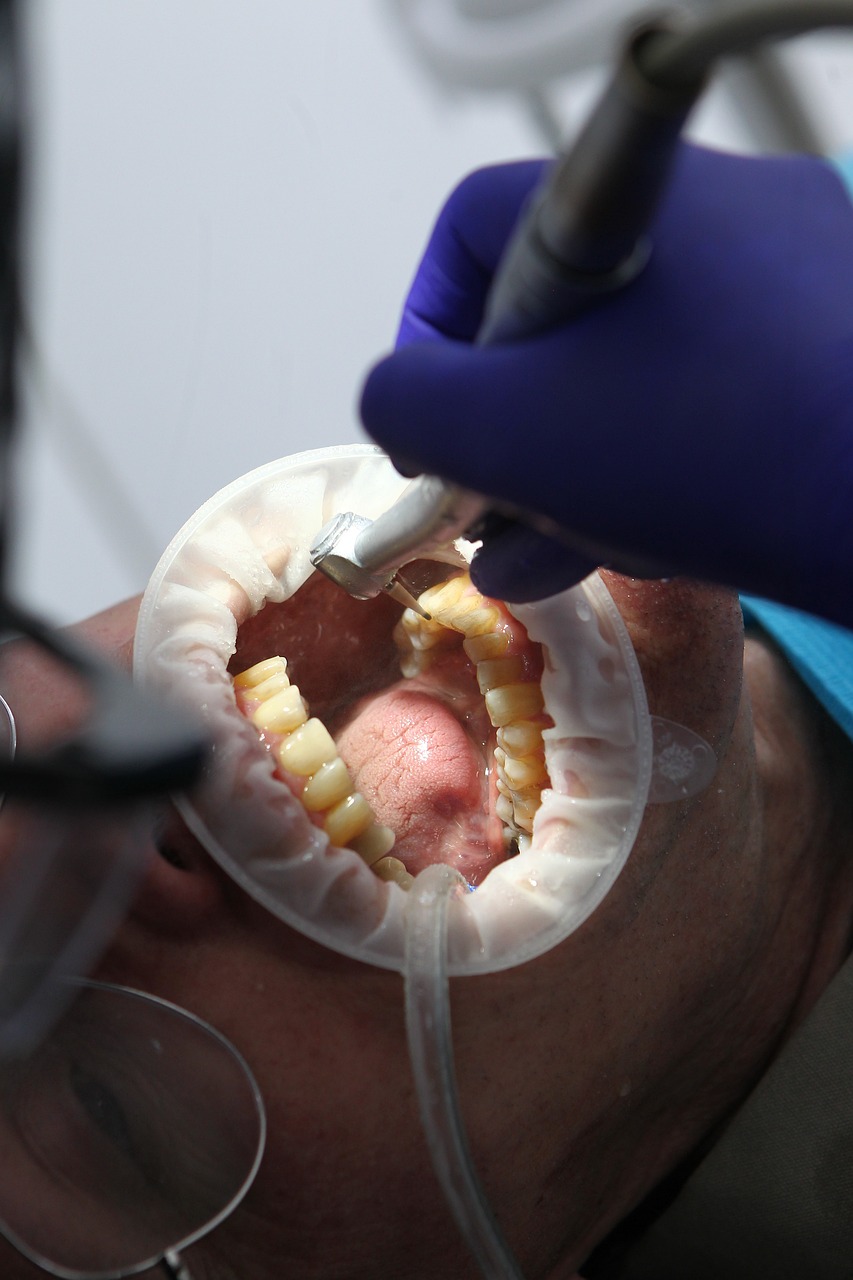

조화로운 치아 관리 루틴을 확립하는 것은 필수적입니다. 불소치약으로 하루에 두 번 양치하고 매일 치실질을 하는 것은 기본적인 습관입니다. 정기적인 치아 검진은 암묵적인 문제를 미리 발견하고 해결하는 데 중요한 역할을 합니다. 또한 끈적끈적한 간식이 적은 균형 잡힌 식단을 섭취하면 우울증을 완화하고 치아를 튼튼하게 유지하는 데 도움이 될 수 있습니다.

예방 관리는 치아 문제가 발생한 후 치료하는 것보다 훨씬 더 효과적이고 비용도 저렴합니다. 구강 건강을 소홀히 하면 충치, 구취, 치아 손실로 이어질 수 있으며, 이는 근관이나 임플란트와 같은 귀중한 치료법을 수반할 수 있습니다. 지금 좋은 치아 위생 관행을 장려함으로써 미소를 위한 더 건강한 미래에 투자하는 것입니다.